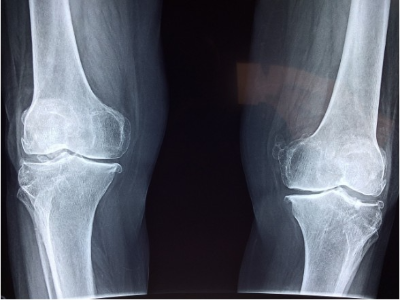

- X-선 검사: X-선 검사는 뼈의 상태를 확인할 수 있는 방법입니다. 연골의 마모 정도나 골절 여부를 알 수 있습니다.